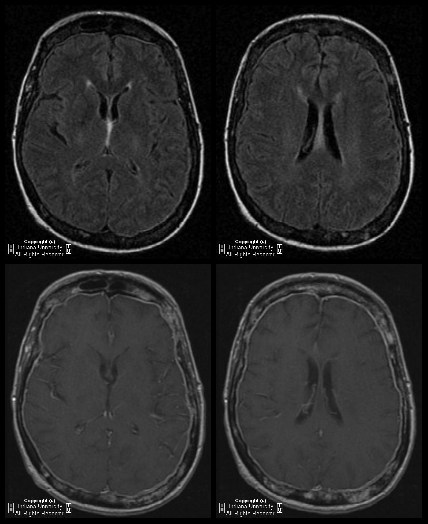

Kallmann syndrome in an adolescent boy Manisha Jana & Atin Kumar Kallmann syndrome was made. An MRI of a normal brain is presented for comparison Hypogonadotropic hypogonadism with associated anos-mia or hyposmia is designated Kallmann syndrome. It is causedbytheabsenceofolfactorynerves ... Read More